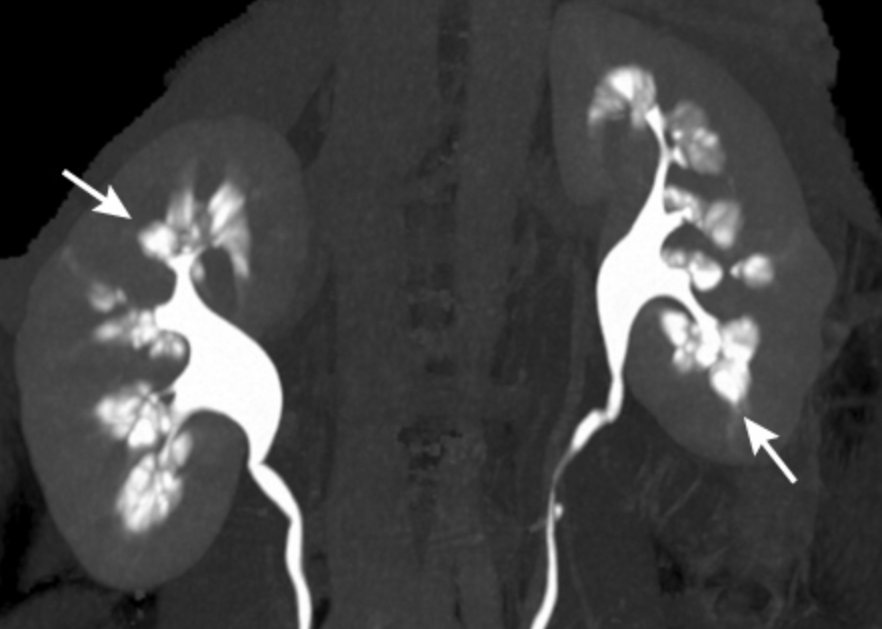

Medullary sponge kidney. Coloured computed tomography (CT) scan in Medullary Sponge Kidney Ribbon Discover the causes, symptoms, and treatment. Medullary sponge kidney is a disease involving the distal nephron that affects less than 1% of the general population. Medullary sponge kidney is a sporadic condition where the medullary and papillary portions of the collecting ducts are. Msk occurs when small cysts (sacs) form. Learn about medullar sponge kidney, a rare condition affecting the. Medullary Sponge Kidney Ribbon.